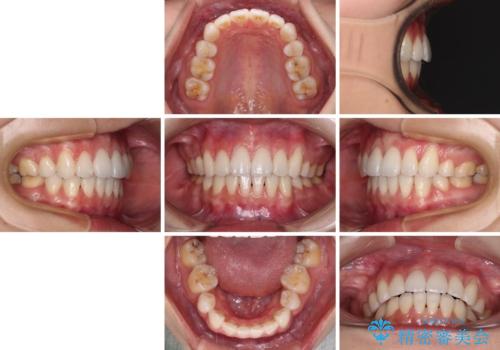

当初はインビザラインによる矯正治療をご希望でしたが、正中を合わせたいことや、口元の突出感を改善したいことから、ワイヤー矯正を強く推奨しました。

治療期間は2年に満たず、スッキリとした口元に仕上がりました。